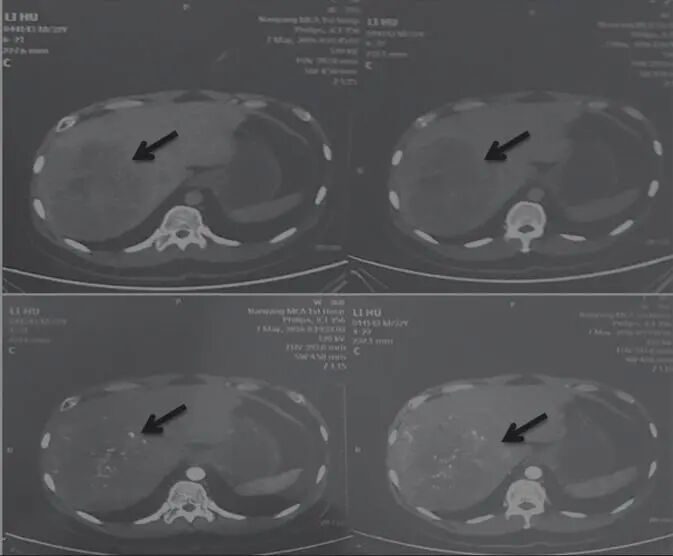

乙肝病史10年,2016年5月7日查AFP 989.8ng/mL,肝右葉巨大占位性病變(圖1),考慮肝癌,大小約15cm×13.2cm,沒有進(jìn)行放療、化療和介入療法。治法:舒少陽(yáng),散結(jié)聚,健脾胃,清濕熱,寧心神

圖1 舒達(dá)少陽(yáng)防治腫瘤驗(yàn)案初診CT結(jié)果